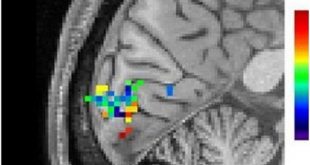

ادامهی نوشتهنیکوتین فعالیت کم مغز در اسکیزوفرنی را اصلاح می کند/دلیل مصرف بالای سیگار در مبتلایان به اسکیزوفرنی